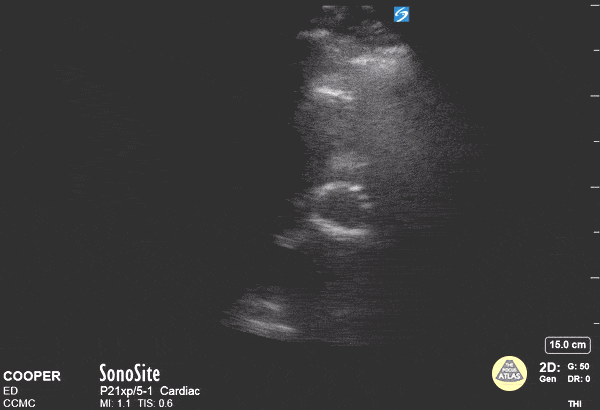

Valvulopathy - TAVR in Short Axis

A 71-year-old male was brought to the ED via EMS for exertional chest pain. The patient was a poor historian and vaguely described a prior cardiac stenting procedure. Bedside echocardiography was performed and demonstrated a hyperechoic ring-shaped structure at the cardiac base when viewed in the parasternal short axis. This structure was determined to be a Transcatheter Aortic Valve Replacement (TAVR). This finding improved the care teams understanding of the patients medical history and altered their evaluation to include pathology of the proximal aorta. Arthur Gross, DO; Max Cooper, MD - Crozer-Chester EM